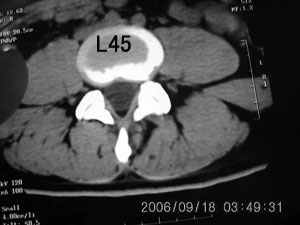

以下是引用守望可可西里在2006-9-18 21:29:00的发言:[br][br] 马尾肿瘤,密度较低,大部分似乎呈囊性变(看着很费眼),考虑室管膜瘤,建议mri。

以下是引用dyg在2006-9-18 22:27:00的发言:[br]正常脊髓.[br]分析:人的脊髓从枕大孔开始至腰1.2椎体为止,有2个生理膨大,分为颈膨大和腰膨大;该病人脊髓须然从腰段开始直至马尾似乎膨大,胆是与上段脊髓密度没有多大变化,所以我认为是正常膨大之延续;当然最好做ct增强或mri检查,排除肿瘤.

以下是引用飞虎在2006-9-18 20:18:00的发言:[br]部分椎管内密度不均且无ct值 故mri检查